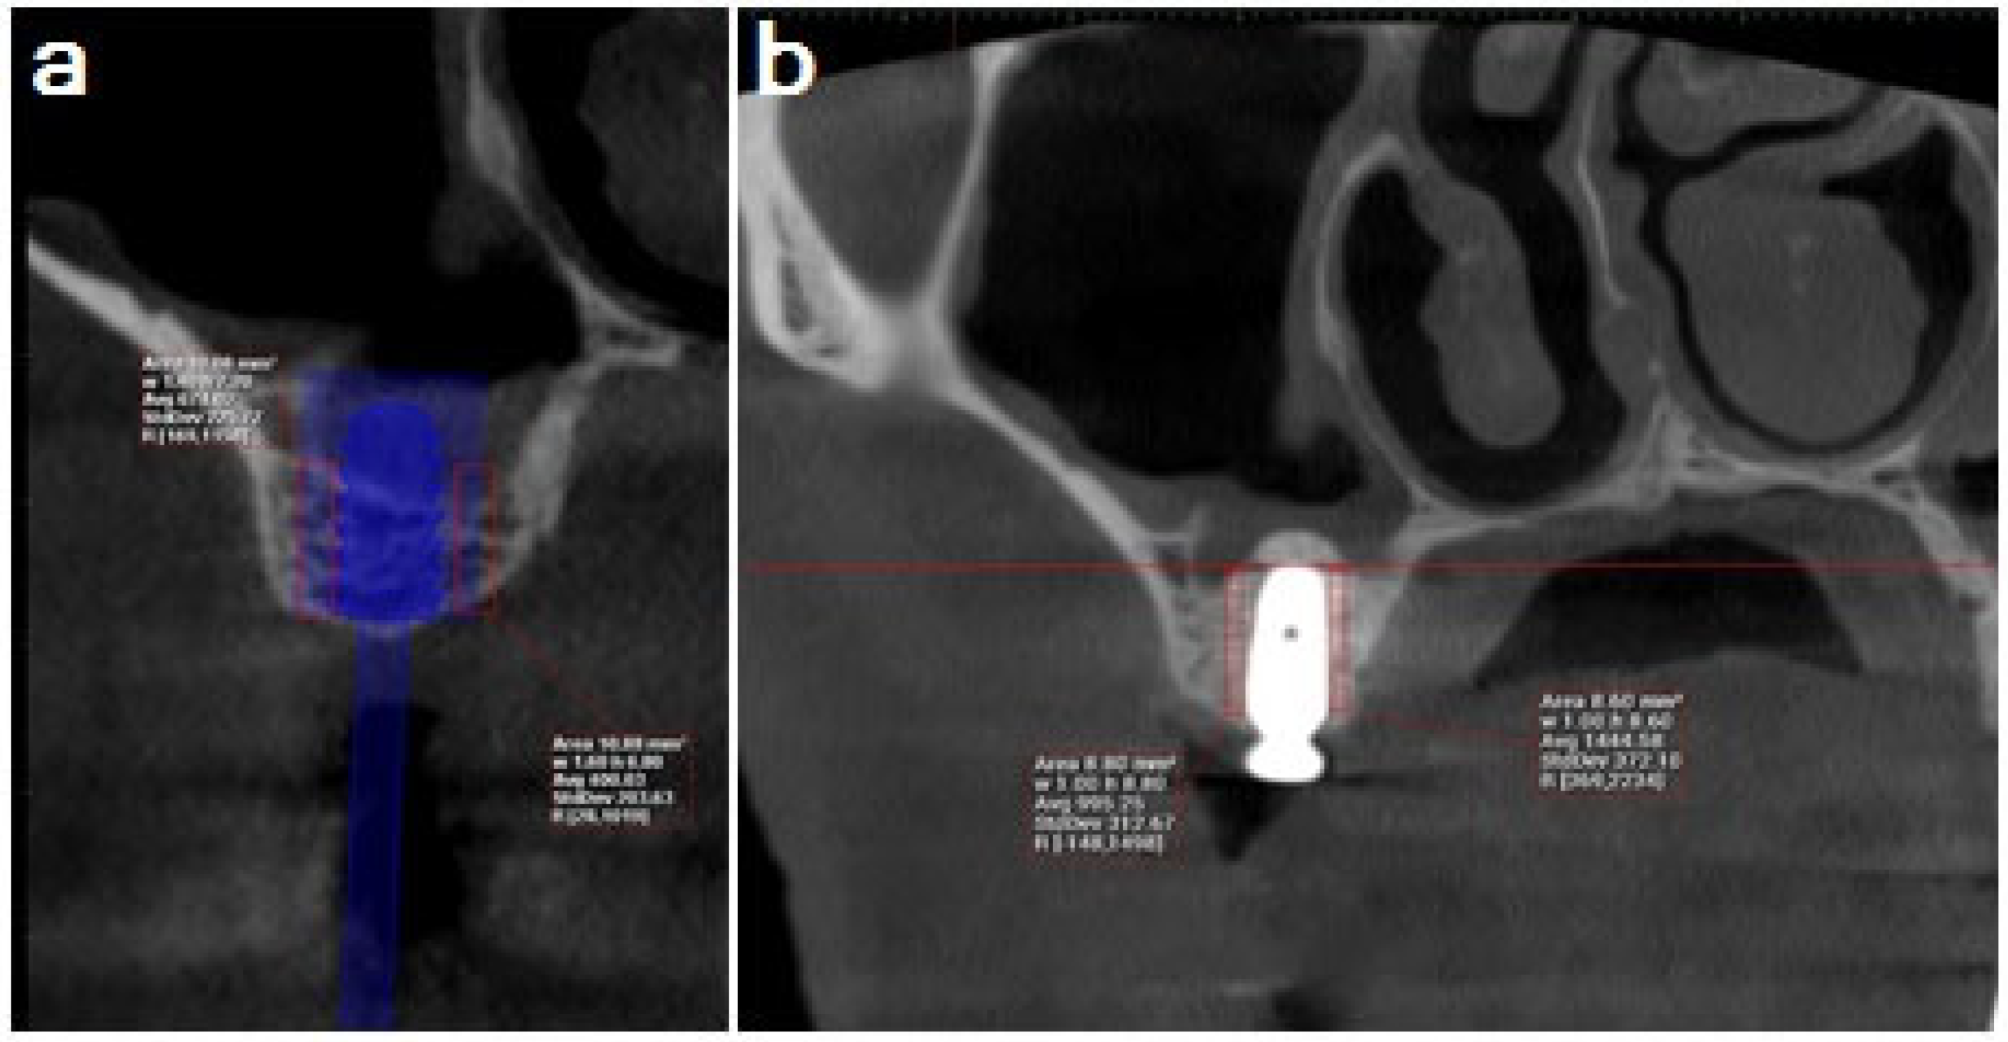

Group 1: Densah sinus lift: The implant motor was switched to reverse-densifying mode (anticlockwise, with a drill speed of 800–1500 rpm, simultaneous with copious irrigation). A 2.2 mm diameter Densah bur was used to make an advanced osteotomy with a wider Densah bur (2.5 mm and 3 mm) by varying the pressure and a pumping motion until it was 1 mm short of the sinus floor. After that, larger Densah drills (3.5 mm and 4 mm) were employed to advance past the sinus floor in increments of 1 mm (Figure 1).

Figure 1. (a) Densah sinus floor elevation; (b) CBCT preoperative cross-section and (c) CBCT cross-section for implant showing the sinus floor elevation after 6 months.